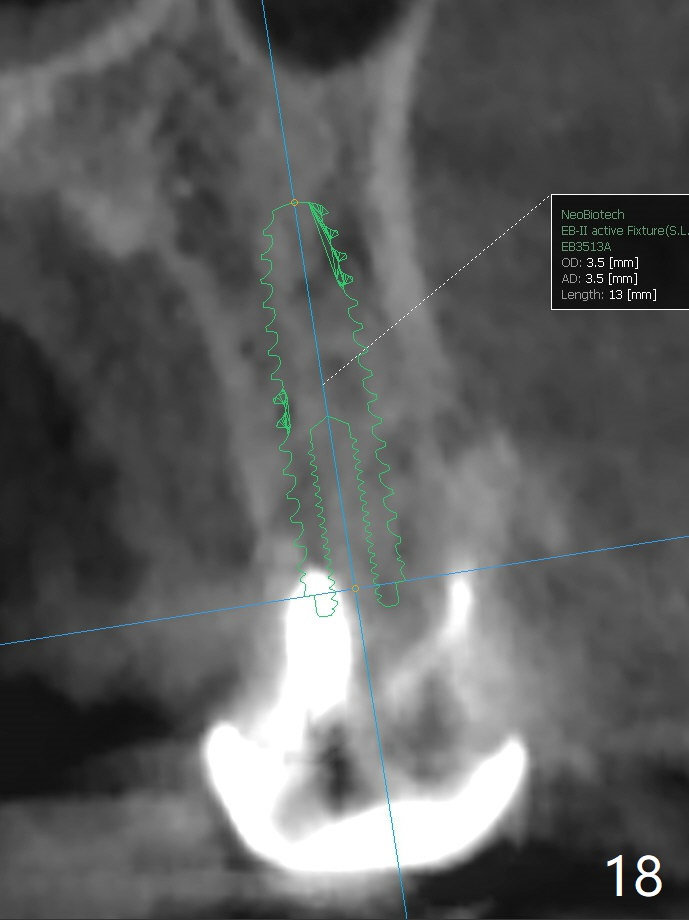

Palatal socket osteotomy, PA to be taken with 2 mm drill, bone graft packed against the buccal wall while the last drill in place